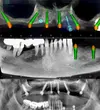

Periimplantitis

Peri-Implant Mucositis

Implant Treatment